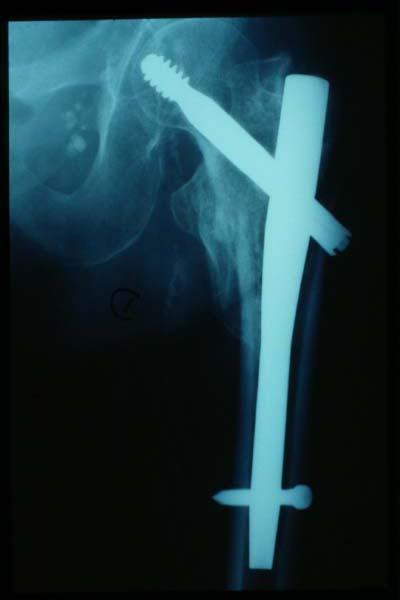

Fractura intertrocantérea de fémur, osteosíntesis

osteosíntesis fractura fémur